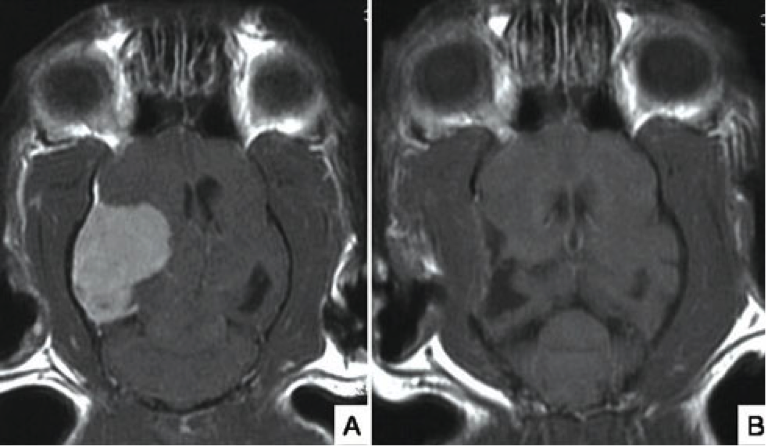

А) МРТ менингиома 11-летнего кота. В) МРТ через 2 месяца после операции.

Опухоли головного мозга являются потенциальной причиной эпилептических припадков, особенно у пожилых кошек и котов.На рисунке А – сканирование показывает наличие большой менингиомы (доброкачественная опухоль в оболочке мозга) у 11-летнего кота, с недавнего времени имеющего эпилептические припадки с дезориентацией (кружение в левую сторону). Этот вид опухоли хорошо поддаётся хирургической резекции с последующим положительным результатом у большинства пациентов. Рисунок В – контрольное МРТ через 2 месяца после операции показывает полное удаление опухоли.